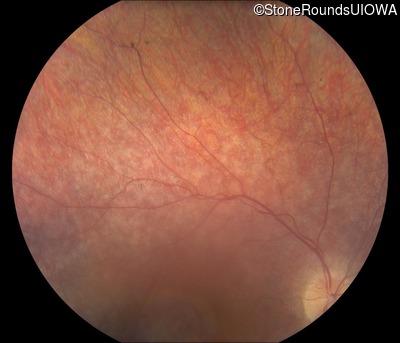

Fundus Photography - Right - 20/50

Exemplar

Fundus Montage - Right - 20/50